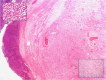

Results: Initial computed tomography scans revealed a lacrimal gland lesion with stable dimensions for more than 1 year and no malignancy features on incisional biopsy. Subsequently, lesion volume growth and bone erosion were documented on orbital computed tomography. Lateral orbitectomy and lacrimal gland resection were performed. Pathology and immunohistochemistry detected Ca ex PA with B-CLL infiltration.